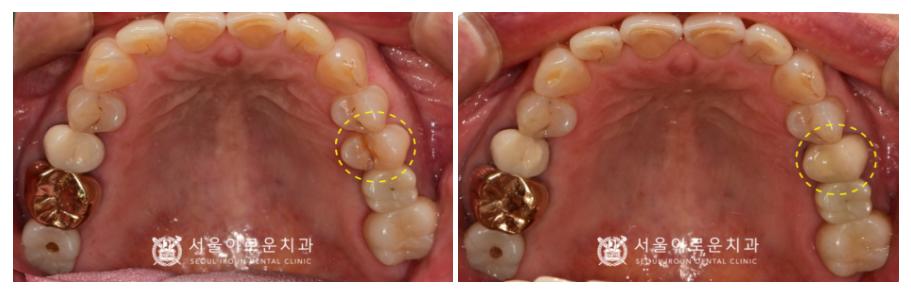

✅ 전 > 후 ✅

(2024.01.22 ㅡ> 2024.03.02)

우선 위턱 왼쪽 두 번째 작은 어금니(#25)의

조각난 치아 부분을 제거 후

꼼꼼하게 신경치료를 완료한 뒤

Post(기둥)을 세워 레진으로 보강하였고,

크라운 제작을 위해 치.아를 다듬었습니다.

크라운 보철물 치료가 마무리 된 모습의

파노라마 사진과 구강 내 사진입니다.

치료 마무리 후에는

파절된 치아를

오래 유지할 수 있도록